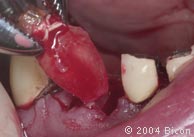

59. |

拔除根管治疗失败的牙齿。 |